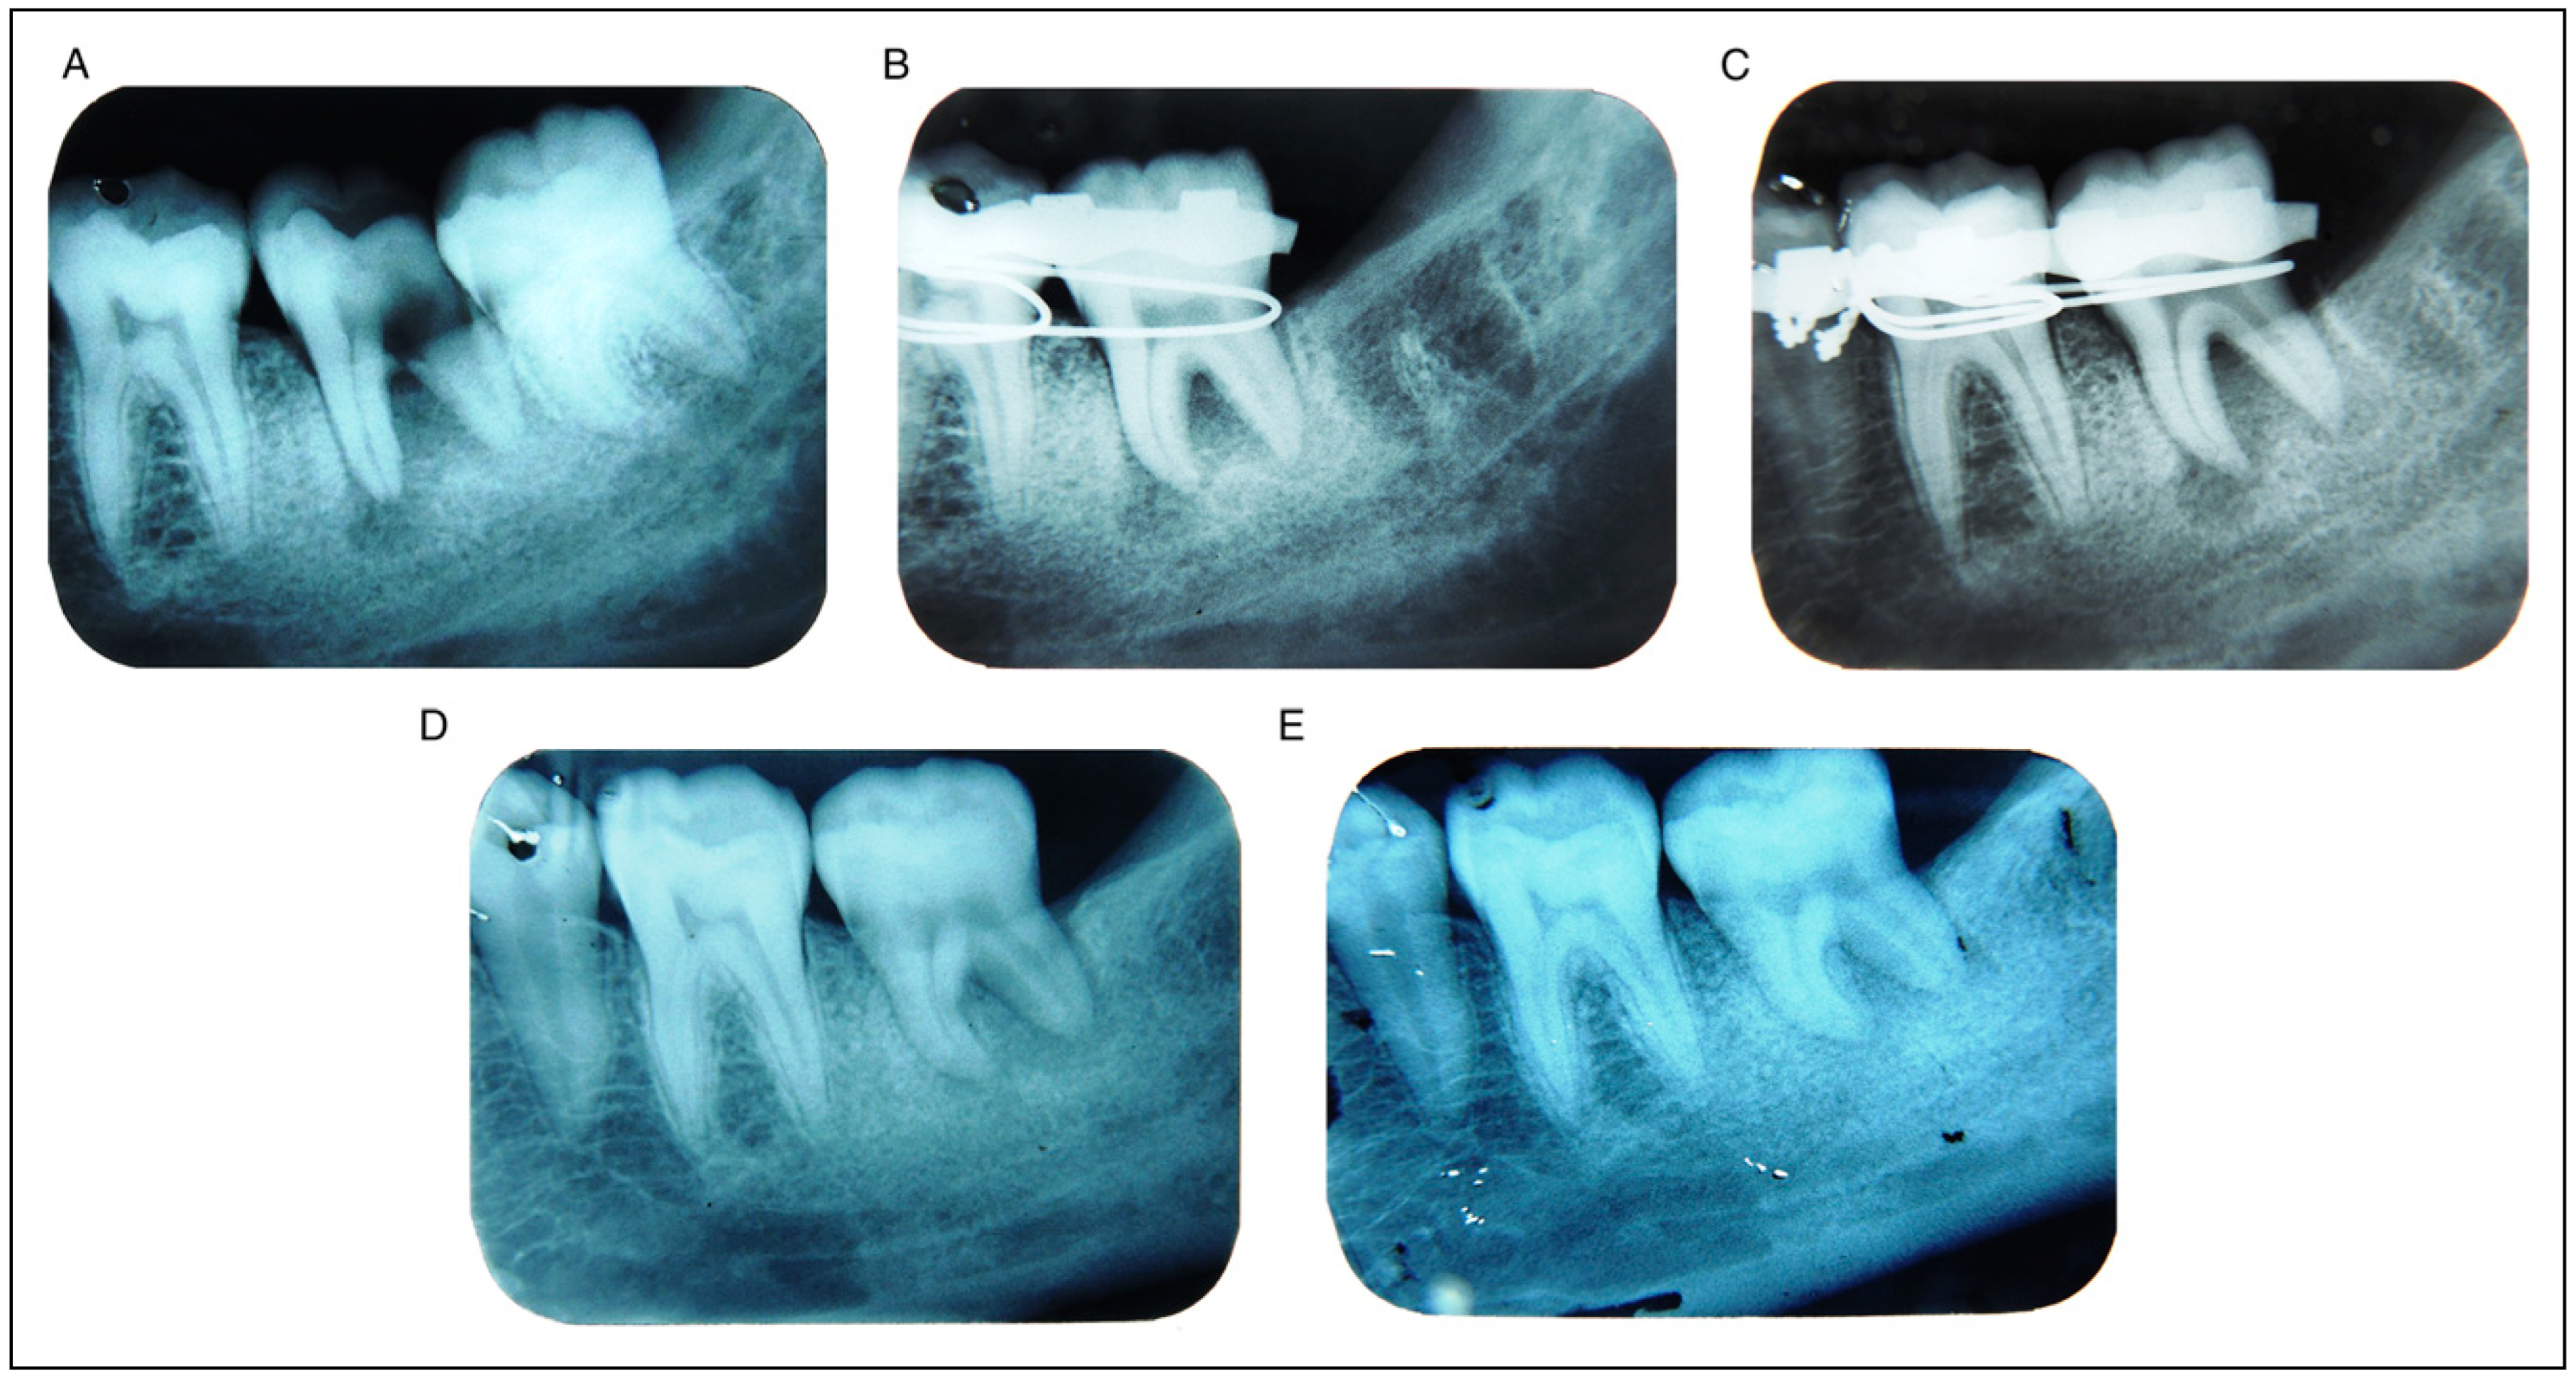

- Detailed case history of all cases which requires extraction of first or second molar were recorded. All patients underwent clinical examination, routine blood investigation, and Intaoral Periapical Radiograph (IOPA), OPG if required.

- On the basis of radiographical examination, the best suitable replica of third molar to be autotransplanted was chosen from the collection of suitable acrylic replicas (Figure 1).

- Mandibular third molar was extracted atraumatically, taking care to avoid damage to periodontal ligament in order to preserve its vitality which is essential for successful outcome of treatment (Figure 5). Simultaneously, precaution was taken not to injure the root surface, and the molar was transplanted into the prepared site with minimum possible lapse of time and less number of attempts to achieve satisfactory fit (Figure 6).

- The transplanted tooth was appropriately splinted with adjacent teeth, and it was left for minimum of 4 weeks (Figure 7).

- Regular clinical and radiographical examinations were performed on prescribed time for follow-up.